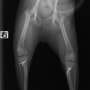

■ 症例22 ポメラニアン 1歳5か月 去勢雄

左後肢の挙上を主訴に来院した。整形学的検査、レントゲン検査より左右の膝蓋骨脱臼(左GradeⅡ〜Ⅲ、右Grade Ⅱ)を認めた。また、脛骨の前方引き出し試験の際に、引き出し兆候は認められないものの、疼痛が認められたため、前十字靭帯の損傷が疑われた。術中における、目視および関節内の操作によって、前十字靭帯の損傷や過伸展といった異常が認められなかったため、膝蓋骨脱臼の整復のみ実施した。手術手技は縫工筋及び内側広筋の解放、脛骨粗面の外側転位、滑車ブロック形造溝術、内外側関節包の縫縮を実施した。本症例は跛行もなく経過良好である。しかし、頸骨高平部の角度(TPA)が 右26.2°、左24.9°であり、解剖学的に前十字靭帯損傷のリスクが高いことから今後の経過に注意が必要である。